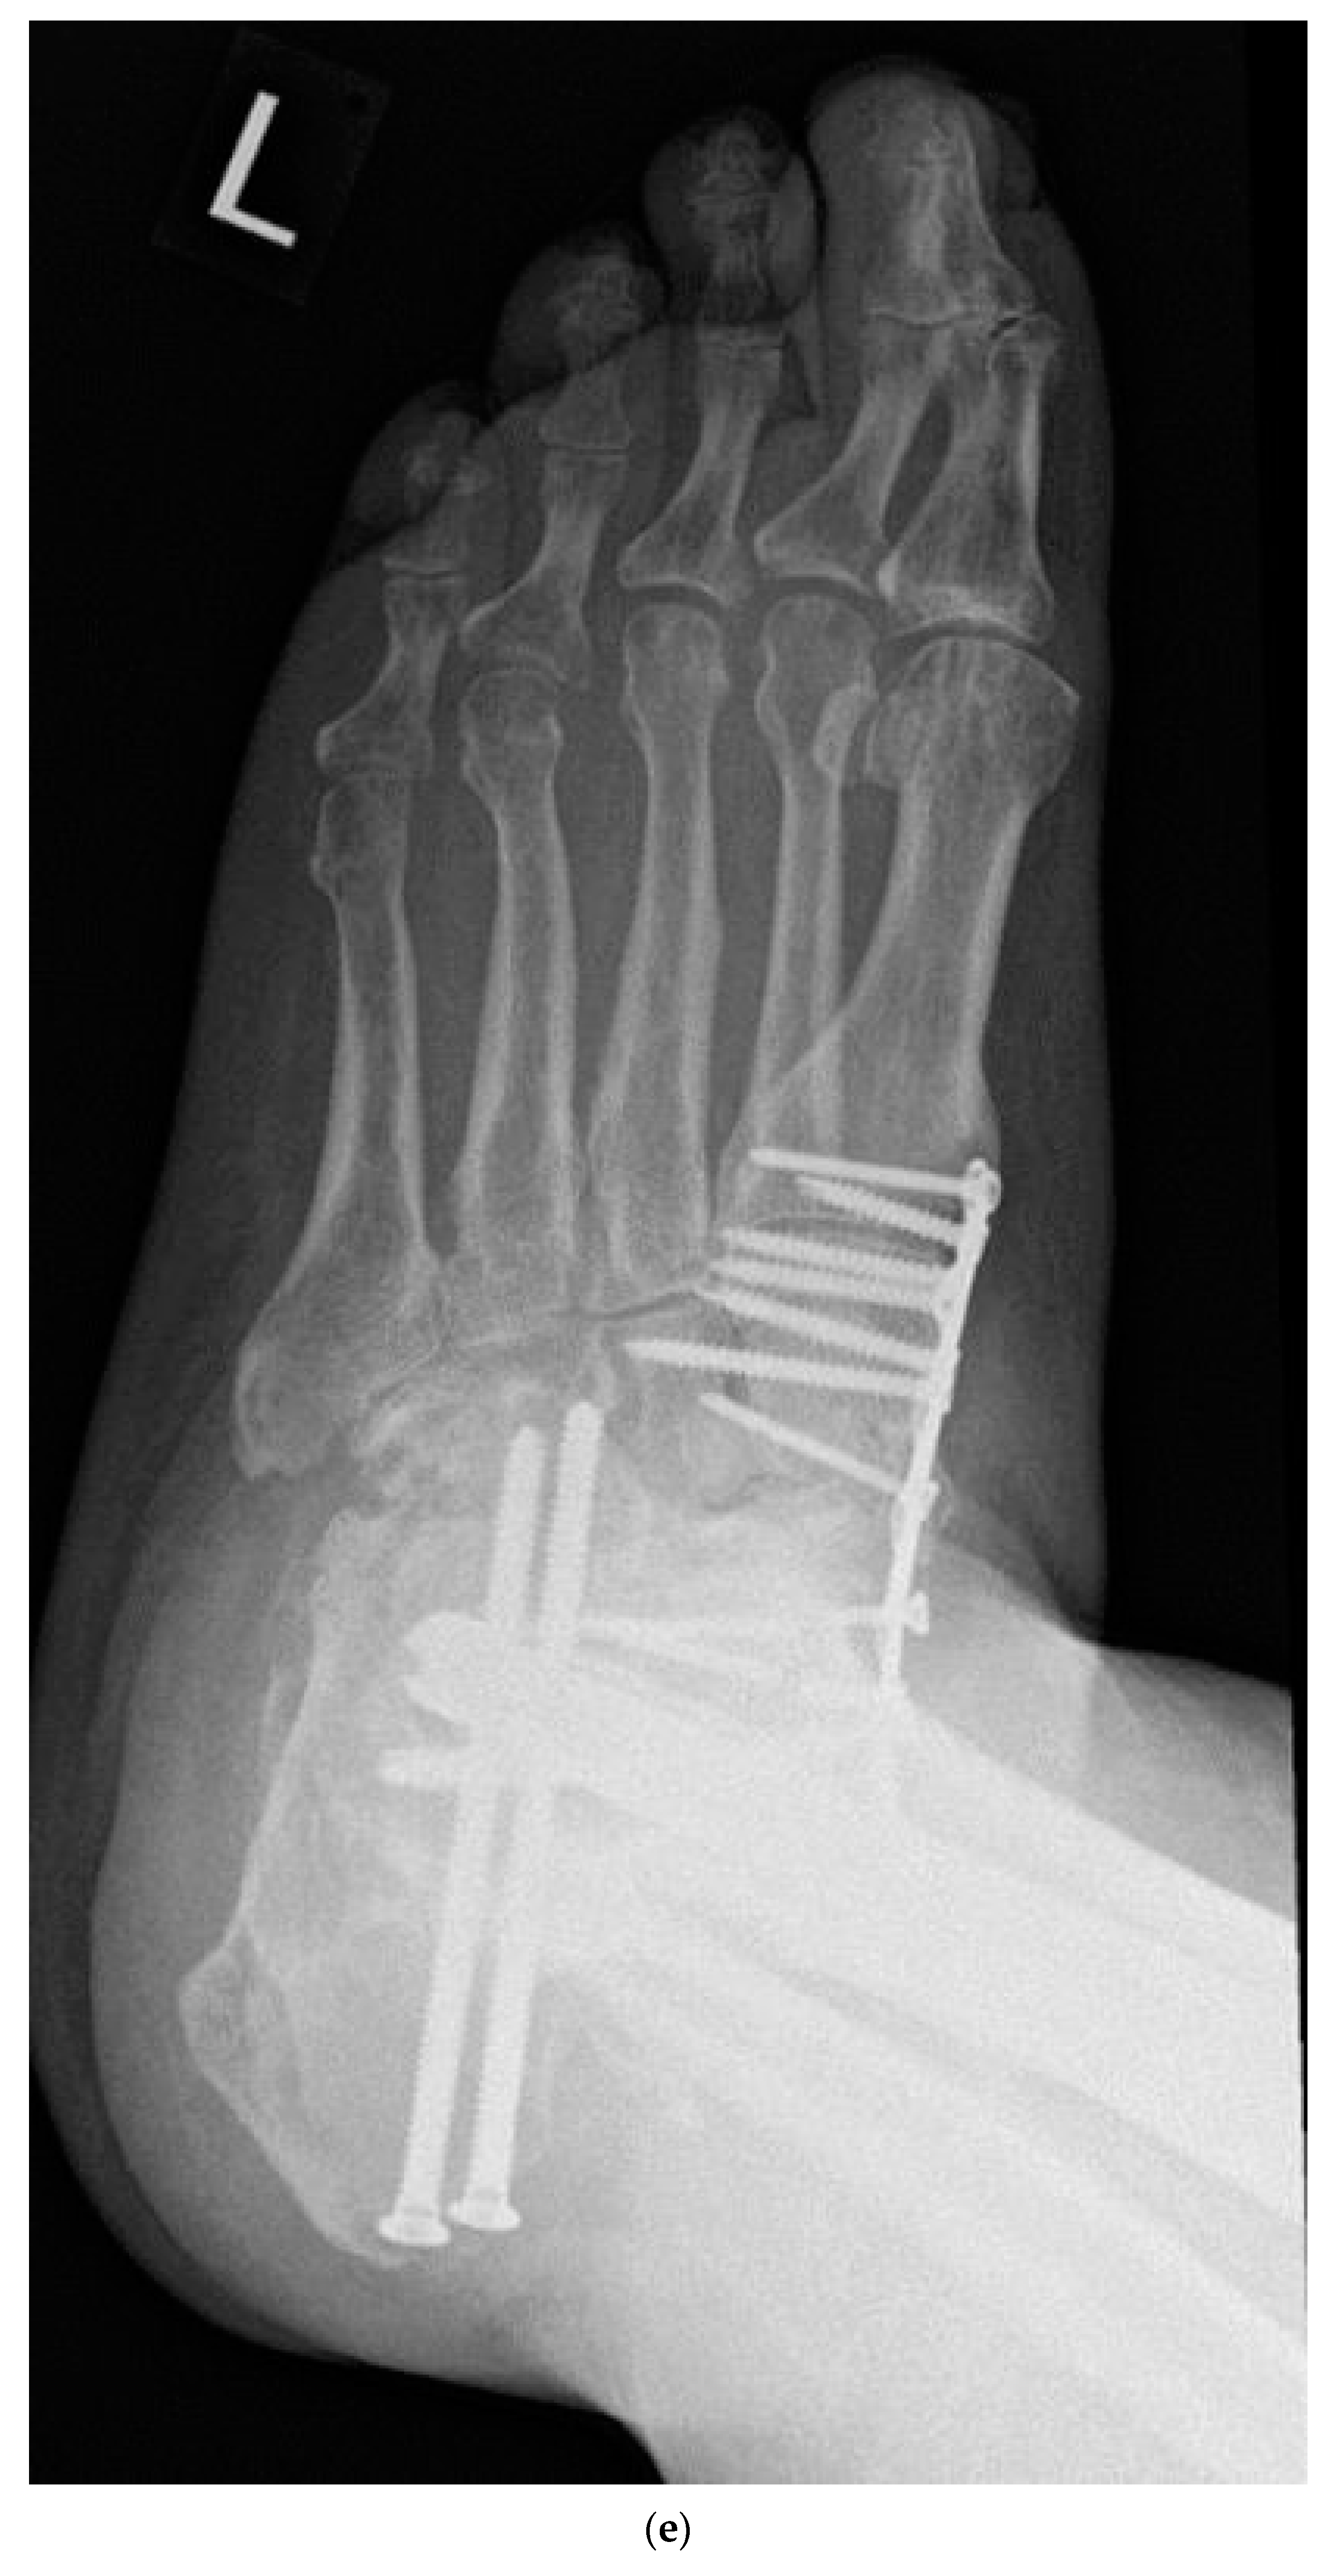

2.4. Surgical Management

- Kavarthapu, V.; Vris, A. Charcot midfoot reconstruction-surgical technique based on deformity patterns. Ann. Jt. 2020, 5, 28. [Google Scholar] [CrossRef]

- Kavarthapu, V.; Budair, B. Two-stage reconstruction of infected Charcot foot using internal fixation: A promising functional limb salvage technique. Bone Jt. J. 2021, 103, 1611–1618. [Google Scholar] [CrossRef]